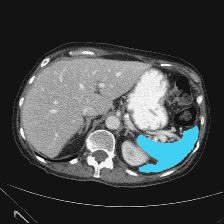

| (a) Ground Truth | (b) Prediction | (c) Heatmap |

In this thorough comparison with top-tier models, our methodology underscores its superiority. To emphasize, the Dice Similarity Coefficient (DSC) of our proposal impressively settles at 82.16%, outclassing formidable contenders like the HiFormer, which rests at 80.39%.

A salient feature of our model is its aptitude for delineating finer anatomical structures. The integration of ISIM markedly amplifies this capability. This prowess is evident in the Gallbladder’s segmentation, where our technique delivers a 71.48% score, overtaking others like the TransDeepLab’s 69.16%. Similarly, the Pancreas, a traditionally intricate organ to segment due to its size, witnesses a conspicuous uplift with our method, achieving 65.02%, surpassing even the FFUNet-trans’s 64.17%.

In the segmentation of more pronounced organs, our model remains unparalleled. The Kidney (L) and Kidney (R) respectively logged scores of 85.45% and 80.85%. Noteworthy is the Liver’s segmentation, where our approach, with a score of 94.85%, nearly mirrors the HiFormer’s 94.61%. Furthermore, in segmenting the Spleen, our model, at 91.62%, slightly edges out our own baseline, which clocked 91.05%.

Reinforcing our point on the model’s capability to harness long-range information, it’s imperative to note our method’s adeptness in segmenting both small and large organs. This demands a considerable receptive field size for precision in object prediction. We further elucidate this with a class activation map for both organ types in Figure 4, shedding light on our model’s enhanced ability to discern local patterns, resulting in meticulous segmentation.